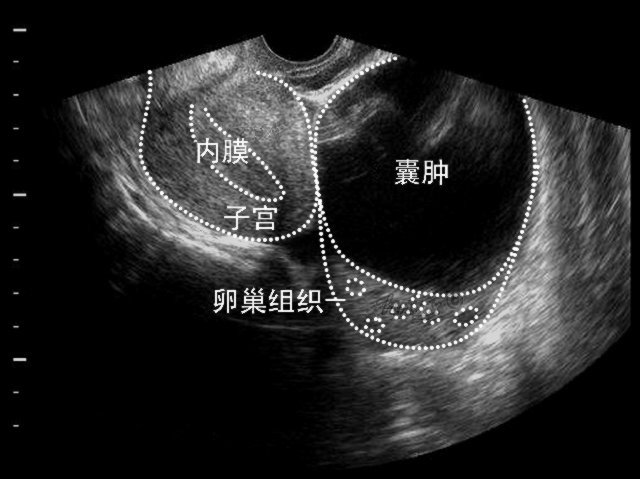

卵巢囊肿是女性常见的疾病之一,生育年龄的女性多见,大多数在早期无明显症状,有一些囊肿慢慢增大后可能出现压迫症状,更严重的一些还会出现破裂、扭转和继发感染等情况。生理性的卵巢囊肿(如黄体囊肿)大多数在月经周期中慢慢长大,等月经结束了就变小或者消失了,病理性的囊肿往往不会自行消失。

卵巢囊肿的早期诊断还是依据检查,如妇科检查、超声、磁共振检查等。如果大一些的时候,有一些可以在腹部摸到的时候,也可以自己发现。早期发现更加重要,把这个任务交给我们专业医务人员吧,你们就不要操心那么多了。